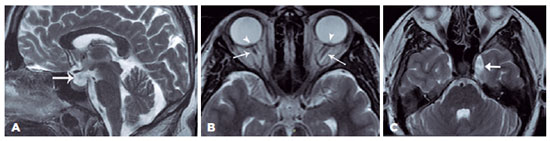

A neurological examination revealed no pathological findings. Cranial magnetic resonance (MR) imaging demonstrated partially empty sella, asymmetric dilatation of the left cavernous sinus, prominent subarachnoid space, and optic disc bulging, suggesting papilledema (Figure 4). MR venography was normal. These imaging results suggest idiopathic elevated ICP in the proper clinical settings. The cerebrospinal fluid (CSF) opening pressure was 310 mmH2O. The patient was diagnosed with PTCS and oral acetazolamide 1 g/day was administered. Visual obscurations, diplopia, and headache improved in two weeks, and tinnitus disappeared completely at six months. Blindspot enlargement on VFE and bilateral papilledema resolved after 2.5 months of treatment (Figure 3).

In our present case, PTCS was diagnosed based on signs and symptoms of increased ICP, papilledema on fundoscopy and OCT examinations, and normal findings on cranial neuroimaging and high CSF opening pressure(1). The key diagnostic MR imaging features of the idiopathic intracranial hypertension included normal or decreased size of the ventricular system, partially empty sella, flattening/indentation of the posterior sclera, prominent optic nerve sheaths, and optic nerve tortuosity. Bilateral transverse sinus stenosis is associated with 90% of cases. The differential diagnosis of the disease may include mild cerebral edema, empty sella syndrome, and hypoplastic dural venous sinuses(10).